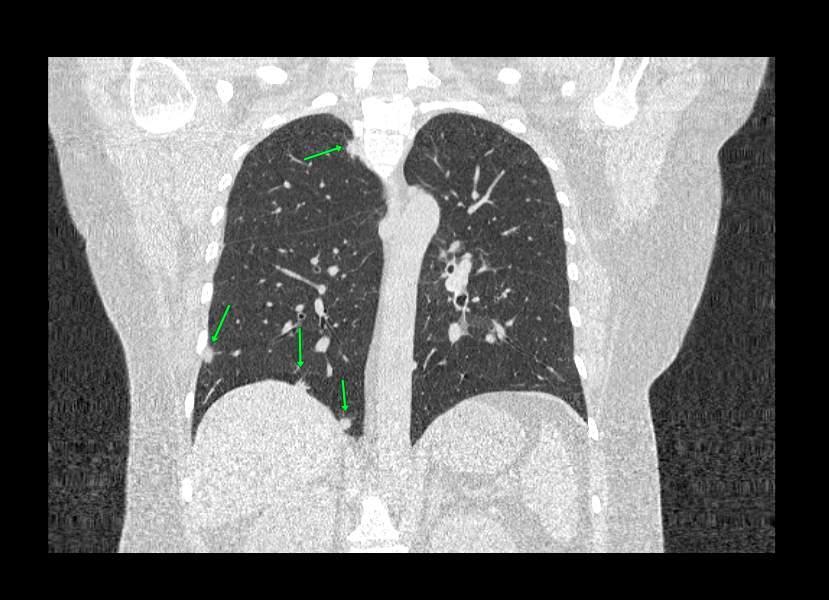

При проведении компьютерной томографии используется тот же принцип прохождения рентген-лучей через ткани с разными плотностями характеристиками. Правда при КТ лучи проходят в разных проекциях под разными углами, формируя множество срезов толщиной до 1 мм, и за счет чего формируется объемное изображение на экране и получается визуализировать мельчайшие патологические изменения. Также высокая четкость и объемность изображения формируется за счет техническими параметрами установок. Рентген-аппарат обладает коэффициентом ослабления в 20%, а КТ установка обладает коэффициентом в 0,5%

КТ и рентгенографию можно также делать с контрастированием для повышения степени детекции злокачественных новообразований и сосудов. Однако, при поиске таких патологий выбор очевиден в сторону КТ, за счет высокой степени визуализации и трехмерности изображения.